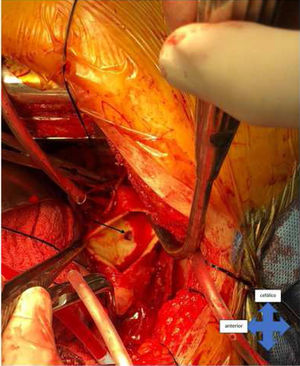

El manejo quirúrgico consistió en realizar doble canulación arterial (axilar y femoral) (figs. 3 y 4) y venosa única (femoral), abordaje mediante toracotomía posterolateral izquierda, disección de aorta torácica y control proximal y distal de la aorta respecto al segmento comprometido por proceso inflamatorio periaórtico. Se utilizó circulación extracorpórea e hipotermia moderada a 30°C, con doble pinzamiento de la aorta torácica, proximal por debajo de la arteria subclavia izquierda (T3) y distal (T6) lo más proximal posible, evitando comprometer la circulación de la médula espinal (T9-T12), logrando una adecuada exploración aórtica, donde se evidenció la rotura de la pared aórtica y una fístula aortoesofágica localizada a nivel de T4 (fig. 5), con proceso inflamatorio que comprometía un segmento de 10cm de la aorta torácica descendente. Al tener varios días de evolución el tejido aórtico inflamatorio, se decidió realizar reemplazo del segmento aórtico con una prótesis de dacrón de 24mm×10cm, control de los vasos intercostales y sutura del borde aórtico al tubo protésico para lograr el control hemostático, técnica de inclusión para evitar incrementar el daño al esófago. El tiempo de isquemia medular fue de 80min, y el de circulación extracorpórea, de 226min.